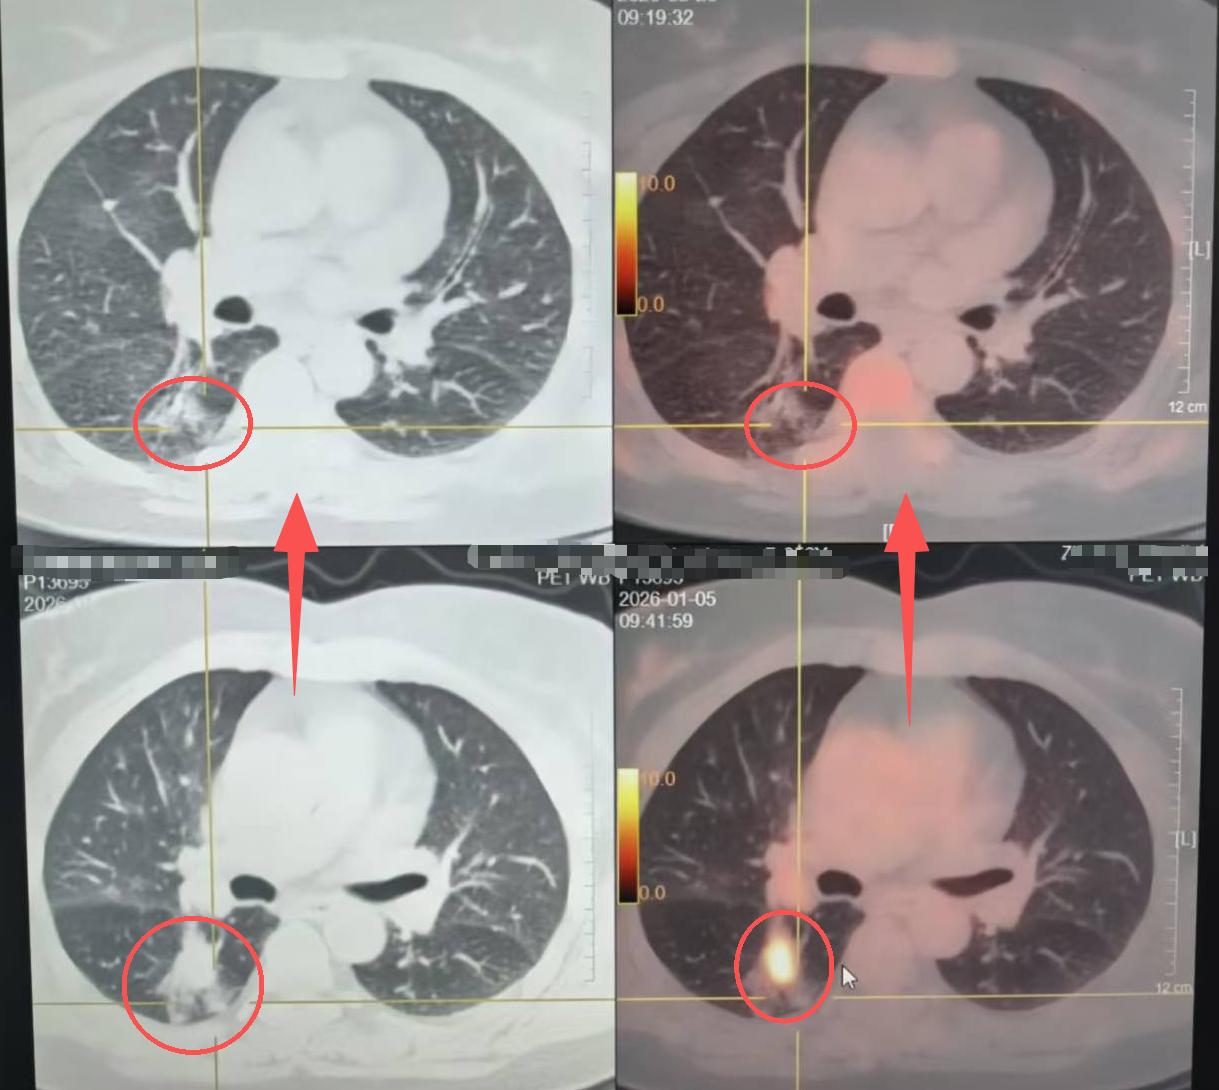

这两位病人都是局部晚期,肿瘤长得特别大,有七八公分,而且还有淋巴结转移——纵隔淋巴结、肺门淋巴结都有,最大的都两三公分。

先经过了3个月的靶向治疗,或者三个疗程的化免,之后我们再给他们安排的手术。

说真的,今天这两个新辅助治疗后的病人,做完手术效果是真的好!肿瘤明显缩小了,淋巴结也消失了,甚至刚刚检测的时候发现,切下来的肿瘤居然全没了,太让人惊喜了。

现在的药是真的神奇。放在以前,这些病人根本没有手术机会,就算治疗,生命可能也就剩一年两年。但现在,这些新的药物,能让肿瘤明显缩小,甚至完全消失,很多病人都能长期存活。